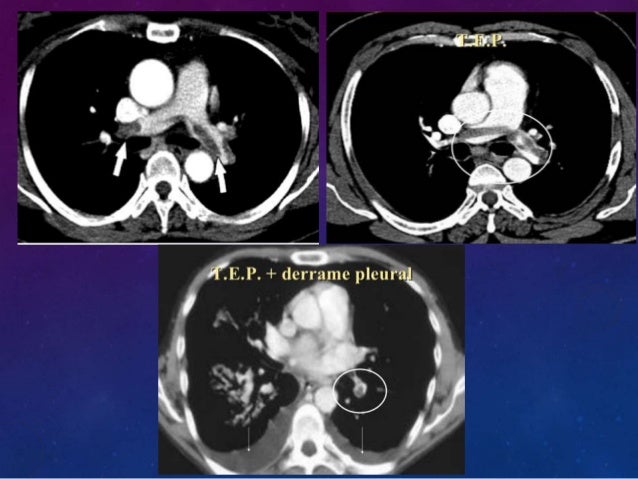

Se realizó angiografía por tomografía axial computada (angioTAC) de arterias pulmonares, que demostró TEP bilateral, que comprometía arterias pulmonares principales, con dilatación de VD ( Figura 1 ), y reflujo del contraste hacia la vena cava inferior, hallazgos que indicaban disfunción ventricular derecha.

Las angioRNM pueden requerir de a 30 minutos. Abstract Acute pulmonary thromboembolism (PTE) is a condition that entails a diagnostic challenge in the usual practice of the primary care emergency departments The difficulty of its diagnosis is found in the heterogeneity of its symptoms. O AngioTAC TEP radiológicamente masivo con signos de hipertensión pulmonar (aumento calibre arteria pulmonar y dilatación VD) 7 O Se comenta de nuevo con UCI y tras valoración del riesgo, se decide ingreso en Neumología con diagnóstico de TEP bilateral 8.

La angiografía pulmonar antiguamente era utilizada como herramienta de oro para el diagnóstico o exclusión de TEP, en la que se documenta un defecto de llene o amputación de una o más las pulmonares en al menos dos proyecciones. AngioTAC de tórax Es el examen de elección para confirmar el diagnóstico de TEP En casos típicos se observa amputación de vasos o defectos del llenado del medio de contraste en el lumen arterial pulmonar de mayor o menor cuantía, dependiendo de la masa trombótica. Snowflake, 4angioTACtrombooclusivopulmonar AngioTAC #, 3 Signo de Westermarck #, img0801 #.